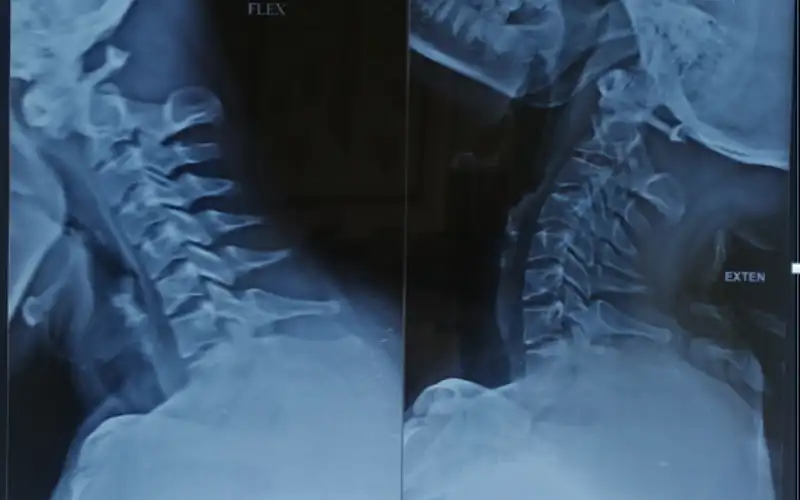

Degenerative cervical spine disorders

The cervical spine is the most flexible anatomic region in the axial skeleton. Distinct segments of the cervical spine give us the ability to perform complex neck motions like head turning, tilting or bending this leads to increase in wear and tear of disc.

The most common degenerative disorders of the cervical spine affect the C3-C7 segments. Symptoms of disc herniation, joint degeneration, and stenosis include neck pain, arm pain and sensory disturbance, weakness, spasticity and difficulty in walking or using hands.

At Kauvery Advanced Spine Centre, minimally invasive approaches can be performed from the back of neck for decompression of nerve roots. Our surgical team also has expertise in motion-sparing operations such as cervical disc replacement and cervical laminoplasty that obviate the need for a cervical spinal fusion.